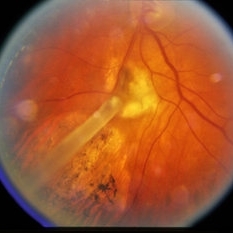

Pre-retinal and retinal hemorrhage.

Condition/keywords: retinal hemorrhage, trauma